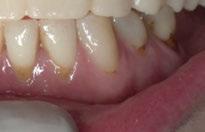

A partir del estudio radiológico y de las imágenes fotográficas podemos observar edentulismo de 17, 15, 14, 12,

25, 26, 28, 37, 38, 47 y 48. Presentaba corona desajustada en 13 con extensión en 12, implantes en 35-36, 45-46, con coronas ferulizadas en 35-36, 45-46, y dientes anteriores superiores con enfermedad periodontal Grado IV.

2. Exploración de tejidos blandos

El paciente presentaba biotipo periodontal grueso, con márgenes asimétricos, con recesiones gingivales a nivel de 11 y 13 y pérdida de tejidos blandos interproximales.